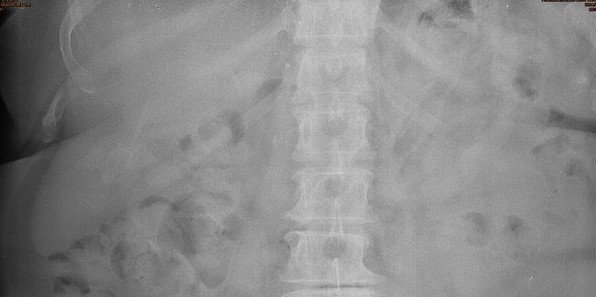

Rigler's/double wall sign :

• Normally only the inner wall of the bowel is visible

• If there is pneumoperitoneum both sides of the bowel wall may be visible

Double wall sign